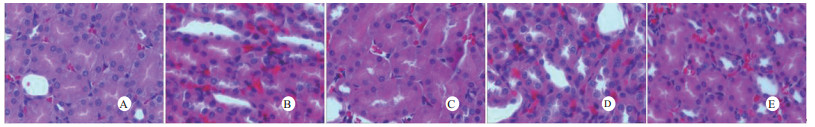

光镜下可见,假手术组肺泡大小形态均匀,结构清晰,肺泡腔内无出血和白细胞浸润;感染性休克组肺泡壁破坏严重,血管壁和肺泡间隔明显增厚;U50488H+感染性休克组大部分肺泡腔均匀一致,肺间隔略增厚,肺泡壁轻度水肿,但出血和白细胞浸润情况比感染性休克组明显减轻(图 1)。假手术组心肌细胞大小一致,排列整齐,核浆比正常,心肌细胞核呈椭圆型,胞浆均匀红染;感染性休克组心肌细胞肿胀,体积明显增大,细胞核大而异型,核内染色质固缩、边集,白细胞浸润明显增加;U50488H+感染性休克组多数心肌细胞形态相对正常,少数心肌细胞呈现脂肪变性(图 2)。假手术组肝细胞结构完整,肝小叶形态正常;感染性休克组肝细胞显著肿胀、呈空泡样和点状/小片状坏死;U50488H+感染性休克组肝细胞轻度肿胀,未见明显坏死灶、肝血窦扩张和炎性细胞浸润(图 3)。假手术组肾组织结构大致正常;感染性休克组肾小管细胞轻度水肿、空泡变性;U50488H+感染性休克组肾小管形态大致正常,间质无明显出血水肿(图 4)。

| A:假手术组,B:感染性休克组,C:U50488H+感染性休克组,D:nor-BNI+U50488H+感染性休克组,E:nor-BNI+感染性休克组 图 1 各组光镜下肺组织病理学改变(HE×400) Fig 1 Histopathological features of lung(HE×400) |